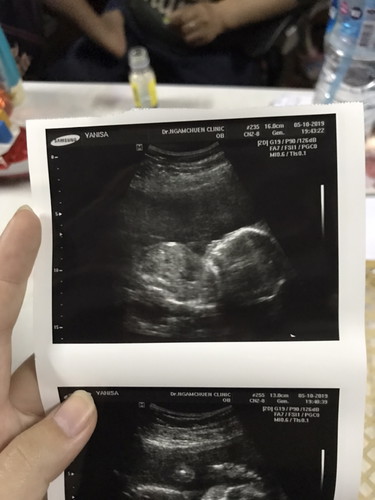

จมูกลูก

มีบ้านไหนซาวด์แล้วจมูกโด่งแบบนี้มั้ยคะ ออกมาจมูกน้องโด่งแบบนี้รึเปล่า? นี่คุณหมอบอกโด่งมาก?

บ้านนี้ตอนซาวด์นี่โด่งได้แม่มาเลยจ้า พอคลอดออกมา .. ดั้งหายคล้ายพ่อทุกระเบียดนิ้ว กลายสภาพเป็นตี๋น้อยเพศหญิงไปเรียบร้อยค่ะ